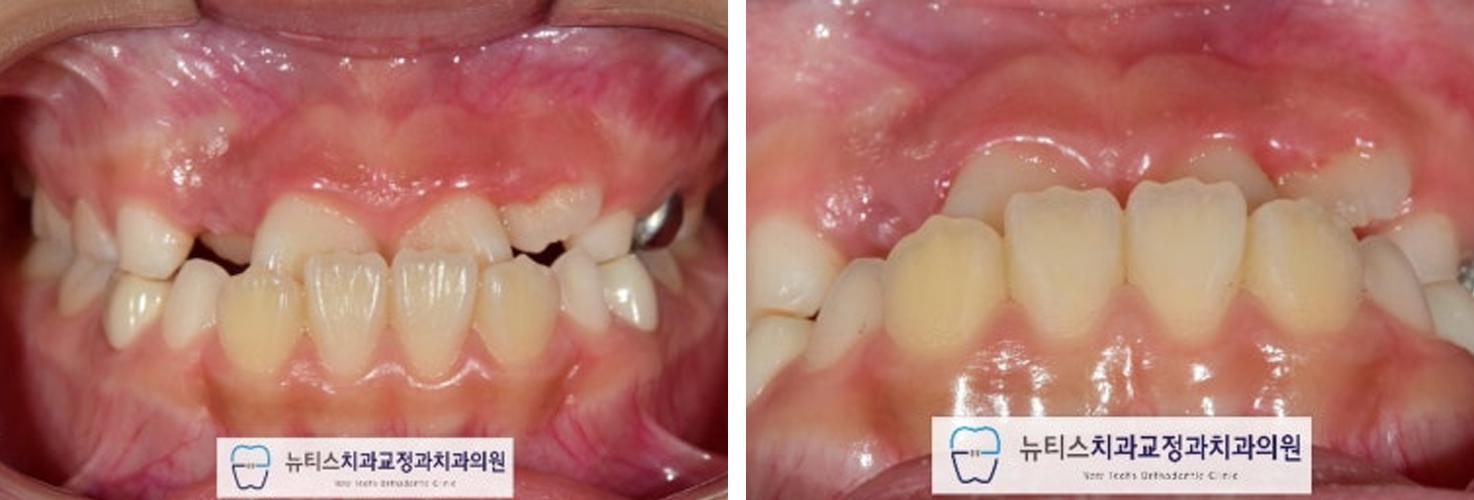

¾È³çÇϼ¼¿ä.ºÎ»ê ±ÝÁ¤±¸ ±¸¼µ¿¿¡ À§Ä¡ÇÑ´ºÆ¼½ºÄ¡°ú±³Á¤°ú Ä¡°úÀÇ¿ø±³Á¤°ú Àü¹®ÀǾȼö¹ü ¿øÀåÀÔ´Ï´Ù. À̹ø ÁÖºÎÅÍ À帶°¡ ½ÃÀ۵ȴٰí ÇÕ´Ï´Ù~Áö³ÁÖ¿¡µµ À帶°¡ ½ÃÀ۵ȴٰí ÇÏ´øµ¥...7¿ùÀº ÈÄ´þÁö±ÙÇÑ ³¯¾¾°¡ À̾îÁö³×¿ä. ÀϱⰡ º¯È¹«»óÇÏ´Ï´Ùµé °Ç° °ü¸® Àß ÇÏ½Ã±æ ¹Ù¶ø´Ï´Ù~ À̹ø¿¡ Æ÷½ºÆÃÇÒ ÄÉÀ̽º´Â"#ºÎ»ê¾î¸°À̹ݴ뱳ÇÕ ÀÔ´Ï´Ù. ¹Ý´ë±³ÇÕÀ» °¡Áö°í ÀÖÀ¸¸é Á¤»óÀûÀÎ ¼ºÀå ¹ßÀ°À» ÇÏÁö ¸øÇÏ¿©ÁÖ°ÆÅÎÀÌ ´õ ½ÉÇØÁú ¼ö ÀÖÀ¸¸ç ºÎÁ¤±³ÇÕÀÌ ¹ß»ýµË´Ï´Ù. ¼ºÀÎÀÇ °æ¿ì ½ÉÇÑ ¹Ý´ë±³ÇÕ Áï, ÁÖ°ÆÅÎÀº ±³Á¤Ä¡·á¸¸À¸·Î ÇØ°áÀÌ ¾î·Á¿ï ¼ö ÀÖÀ¸³ª ¼ºÀå±â ¾î¸°ÀÌÀÇ °æ¿ì¿¡´ÂÁ¤»óÀûÀÎ ¼ºÀå ¹æÇâÀ¸·Î À¯µµÇØ º¼ ¼ö ÀÖ½À´Ï´Ù. À̰¡ Ʋ¾îÁö°í µ¡´Ï°¡ Àְųª °ø°£ÀÌ ¸¹ÀÌ ÀÖ´Â °æ¿ì¿¡´Âº¸È£Àںв²¼ ÀÎÁö°¡ ºü¸£³ªÀÌ·± ºÎÁ¤±³ÇÕ (¹Ý´ë±³ÇÕ) À» °¡Áö°í ÀÖÀ¸¸é Àß ¸ð¸£½Ã´Â °æ¿ì°¡ ¸¹½À´Ï´Ù. ÈçÈ÷ ¾Þ±Û¾¾ 3±Þ ºÎÁ¤±³ÇÕÀ̶ó°í Çϴµ¥À̸¦ ¹æÄ¡ÇÏ°Ô µÇ¸é ³ªÁß¿¡ ¹®Á¦°¡ Å©°Ô µÉ ¼ö ÀÖÀ¸´Ï°¡±ÞÀû ºü¸¥ Á¢±ÙÀÌ ¿ä±¸µË´Ï´Ù.(¾ÆÀÌ º¸Çè¿¡¼ º¸ÀåÇØ ÁÖ´Â °æ¿ìµµ ÀÖ½À´Ï´Ù) #ºÎ»ê¾î¸°À̱³Á¤Ä¡°ú ÀÎ ÀúÈñ ´ºÆ¼½º¿¡¼´Â¼ö¿ÏºÎ (¼Õ»À) ¿¢½º·¹À̸¦ ÅëÇØ¿ì¸® ¾ÆÀÌÀÇ ¼ºÀå ´Ü°è¸¦ ÆÇ´ÜÇÏ¿© °¡Àå ÀûÀýÇÑ ½Ã±â¿¡ Ä¡·á¸¦ ÁøÇàÇÒ ¼ö ÀÖµµ·Ï ÇØ µå¸³´Ï´Ù. À̰¡ ¹Ý´ë·Î ¹°¸°´Ù°í ÇÏ¿©#ºÎ»ê¾î¸°À̱³Á¤Ä¡°ú ÀÎ ÀúÈñ ´ºÆ¼½º·Î³»¿øÇϽŠºÐÀÔ´Ï´Ù.ÃÊÁø »çÁøÀÔ´Ï´Ù.È¥ÇÕÄ¡¿±â ´Ü°è·Î ÇöÀç ¾Õ´Ï°¡ ¹Ý´ë·Î ¹°¸®°í ÀÖ½À´Ï´Ù. ÀÌ·¯ÇÑ #ºÎ»ê¾î¸°À̹ݴ뱳ÇÕ À» º¸ÀÌ´Â °æ¿ì¿¡´ÂÁ¤»óÀûÀÎ ÅÎÀÇ ¼ºÀåÀ» ÀúÇØÇÒ ¼ö ÀÖ½À´Ï´Ù. ¹æ»ç¼± »çÁø¿¡¼µµ¾Õ´ÏÀÇ ¹Ý´ë±³ÇÕÀ» È®ÀÎÇÒ ¼ö ÀÖ½À´Ï´Ù. #ºÎ»ê¾î¸°À̱³Á¤Ä¡°ú ÀÎ ÀúÈñ ´ºÆ¼½º¿¡¼´Â¿©·¯°¡Áö °Ë»ç¸¦ ÅëÇÏ¿© ÇÁ¸®¿Ã¼Ò¶ó´Â ÀåÄ¡¸¦ »ç¿ëÇÏ¿©#ºÎ»ê¾î¸°À̹ݴ뱳ÇÕ À» °³¼±Çϱâ·Î ÇÏ¿´½À´Ï´Ù.  Ä¡·á ÈÄ »çÁøÀÔ´Ï´Ù.

#ºÎ»ê¾î¸°À̹ݴ뱳ÇÕ ÀÌ °³¼±µÇ¾ú°íÀüÄ¡ºÎÀÇ ±³ÇÕ°ü°è°¡ ¾çÈ£ÇØ Á³½À´Ï´Ù. Ä¡·á ÈÄ ¹æ»ç¼± »çÁø¿¡¼µµ¹Ý´ë±³ÇÕÀÌ °³¼±µÈ °ÍÀ¸·Î È®ÀÎÇÒ ¼ö ÀÖ½À´Ï´Ù.(Ä¡·á±â°£ 6°³¿ù)  Ä¡·á Á¾·á ÈÄ 1³â Áö³ »çÁøÀÔ´Ï´Ù. #ºÎ»ê¾î¸°À̱³Á¤Ä¡°ú ÀÎ ÀúÈñ ´ºÆ¼½º¿¡¼´Â¹Ý´ë±³ÇÕÀ» °³¼±ÇÑ ÀÌÈÄ, À¯Áö°¡ Àß µÇ´ÂÁö ´Ù¸¥ ¹®Á¦°¡ ¾ø´ÂÁö ÁÖ±âÀûÀΠüũ¸¦ ½ÃÇàÇÕ´Ï´Ù. ÃÊÁø, Ä¡·á ¸¶¹«¸®, 1³â À¯Áö üũ »çÁøÀÔ´Ï´Ù. Àß À¯Áö°¡ µÇ¾ú°í ÀûÀýÇÑ ½Ã±â°¡ µÇ¸é2Â÷ ±³Á¤À» ÁøÇàÇÒ ¿¹Á¤ÀÔ´Ï´Ù~ #ºÎ»ê¾î¸°À̹ݴ뱳ÇÕ ÀÇ °æ¿ì¿¡´ÂÄ¡·áÀÇ Å¸À̹ÖÀÌ Áß¿äÇϱ⠶§¹®¿¡ Àü¹®°¡¿Í »ó´ãÇÏ´Â °ÍÀÌ Áß¿äÇÕ´Ï´Ù. #ºÎ»ê¾î¸°À̱³Á¤Ä¡°ú ÀÎ ÀúÈñ ´ºÆ¼½º¿¡¼´Â¿ì¸® ¾ÆÀÌ¿¡ ´ëÇÏ¿© ´Ù¾çÇÑ °Ë»ç¸¦ ÅëÇØÃÖÀûÀÇ Ä¡·á ¹æ¹ýÀ» µµ¸ðÇØ µå¸®°í ÀÖ½À´Ï´Ù. Ȥ½Ã ¿ì¸® ¾ÆÀÌÀÇ Ä¡¾Æ°¡ ¹Ý´ë·Î ¹°¸°´Ù´øÁö¾ÕÀ¸·Î »ÀÃÄÁ³´Ù¸é ¾ðÁ¦µçÁö ¸Á¼³ÀÌÁö ¸¶½Ã°íÀúÈñ ´ºÆ¼½º·Î ¿¬¶ô ÁÖ¼¼¿ä~